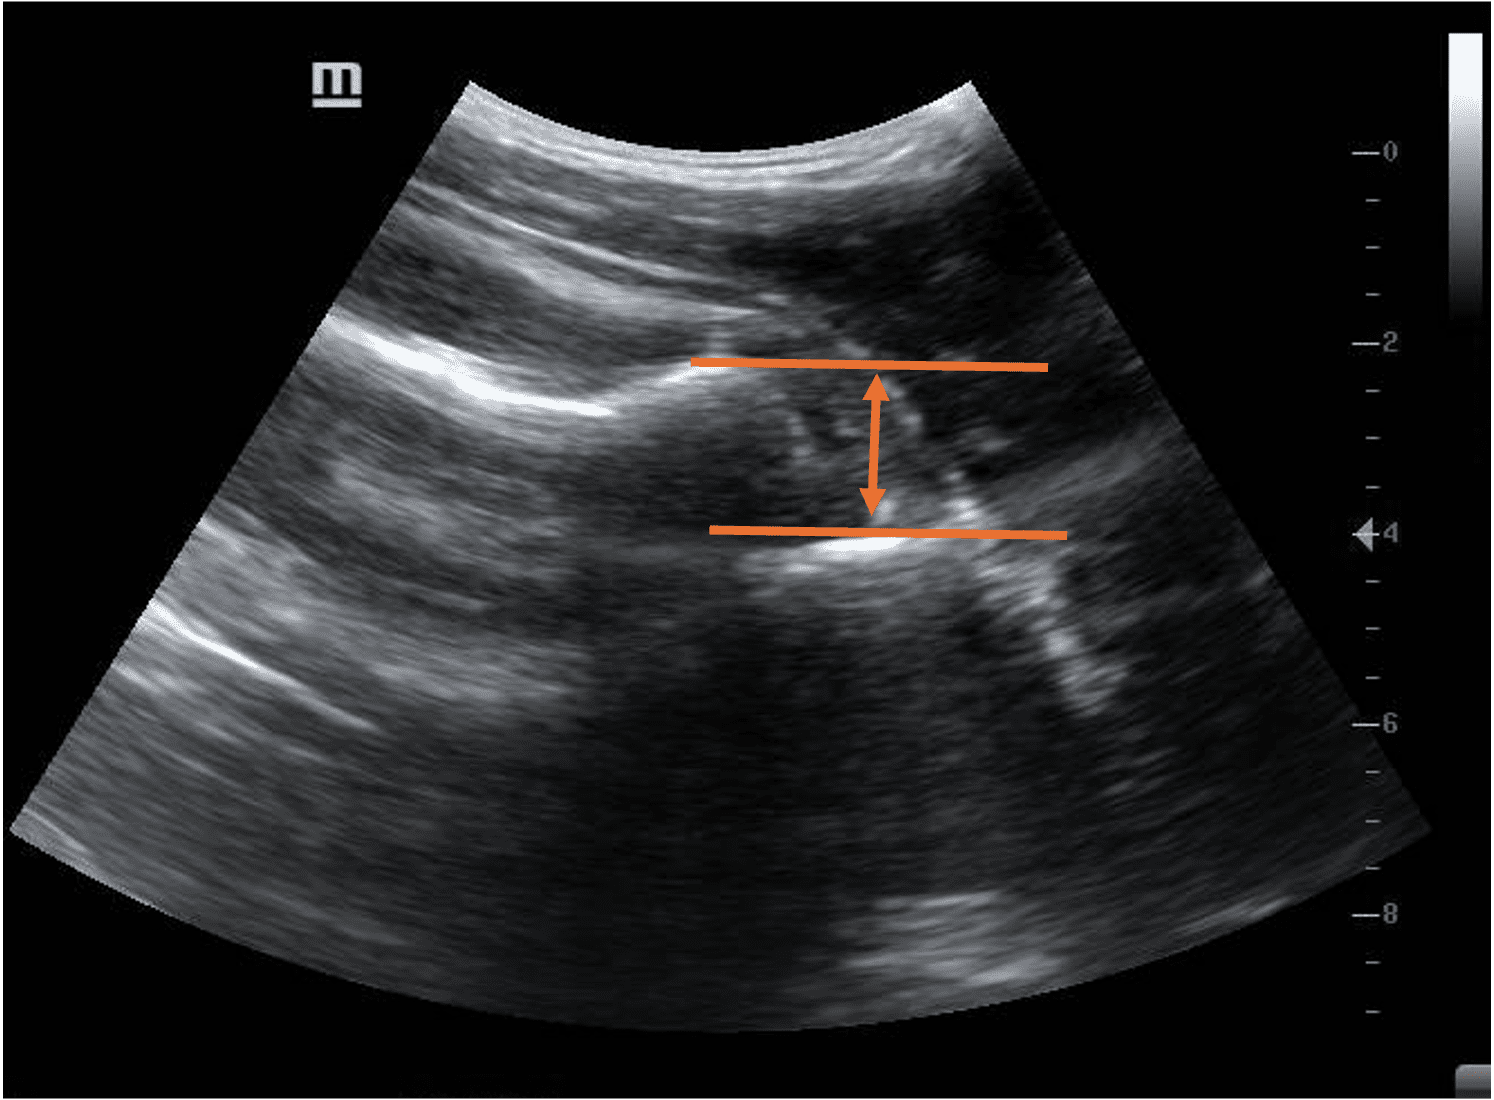

Figure 7. Pre-reduction (left) and post-reduction (right) images of right shoulder joint

Yes

The head of the humerus appears to be deeper in position compared to the glenoid rim on the first image. This indicates an anterior shoulder dislocation. The head of the humerus is in line with the glenoid rim in the image on the right, indicating successful reduction

Further confirmation of the reduction can be done by observing the head of the humerus on ultrasound while rotating the affected shoulder internally and externally with the arm adducted. The head will appear to move smoothly within the glenoid rim.